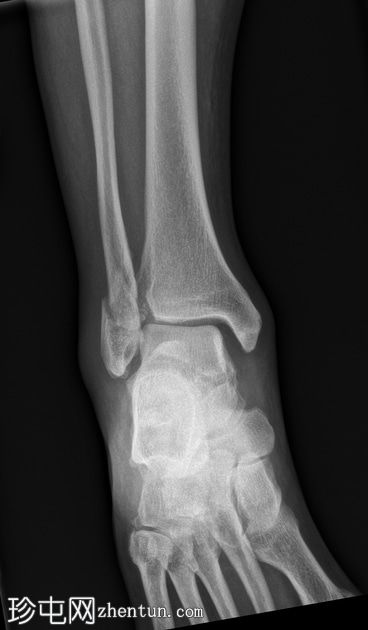

1.jpg

正面

腓骨下端轻度螺旋形骨折,位于下胫腓联合水平(Weber B),骨折移位,伴有轻度软组织肿胀。

踝关节内侧间隙增宽6毫米(正常值<4毫米),胫腓间隙增宽,胫腓重叠减少,这些表现提示胫腓联合损伤和踝关节不稳定。

踝关节内侧软组织阴影,提示内侧副韧带损伤。

后踝(踝骨)骨折轻微移位。

可见腓籽骨。

足底跟骨骨刺。

可见跟腱末端钙化性病灶。